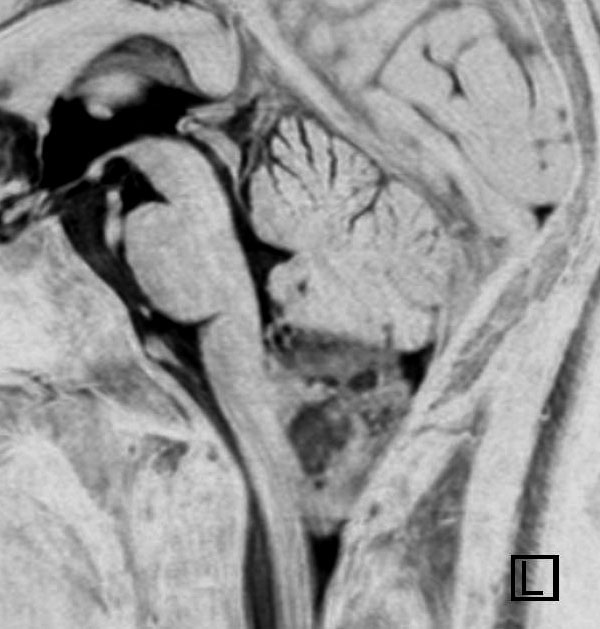

第4脳室床に発生した典型的な上衣腫 EPN-PFA の画像です。水頭症になって,頭痛と嘔吐,意識障害で発症しました。典型的なMRI画像と病理所見です。MRIでは第4脳室からマジャンディー孔を越えて脊髄背側まで長く腫瘍が伸びています。腫瘍内部に小さなのう胞が複数みられます。病理像では,血管周囲に細胞核がない無核野が認められます。血管周囲に伸びた繊細な単極性突起が集まった領域です。これは,血管周囲偽ロゼット perivascular pseudorosette という上衣腫に特徴的な病理所見です。

幼児の巨大な上衣腫です。左ルシュカ孔から延髄を取り囲む様に小脳延髄角槽に進展しています。最も典型的で治療が難しいタイプです。これはT2強調画像ですが,ガドリニウム増強されないものでした。

左が術前,右が術後です。脳底動脈の周囲が摘出できませんでした。幼児ですが手術後には局所照射をするしか方法がありません。